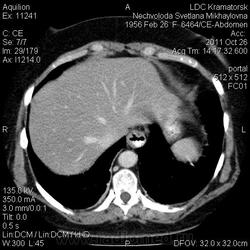

Здравствуйте! Вот уже месяц не могут поставить диагноз. Первичный очаг найти не удалось. Множественная миелома (несекретирующая?, т.к. по крови стерн. пункция не дает результата)?

Была взята биопсия с пораженного позвонка, но в материале оказалось мало клеток кости, наличие фиброзных клеток. Материал трепанбиопсии правой подвздошной так же содержал мало клеток, т.к. удалось углубиться всего лишь на 7мм (дальше сломалась игла, по словам врача скорее всего об фиброзное образ.). Можно ли по результатам КТ предложить повторный, более прицельный поиск? Что еще говорит КТ?

По имеющимся файлам-дайком я не нашла признаков опухоли. Имеется множественное остеолитическое поражение позвоночника, ребер, грудины, частично - таза. Лимфоузлы не увеличены. Тоже поставила бы на первое место миеломную болезнь. Диагностирование её не всегда простое дело. Поражена грудина и, наверное, нужно посоветоваться с онкологом (гематологом) стоит ли сделать стернальную пункцию.Советую написать в личку tatyana.

Думаю тоже в первую очередь здесь миеломная болезнь, процентов на 80%. Но результаты лабораторных анализов действительно неоднозначные.

Повторюсь: по имеющимся данным наиболее вероятной считаю миеломную болезнь